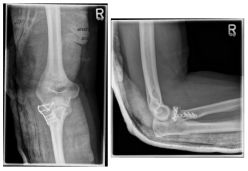

Photo: An undislocated fracture that can be treated conservatively.

- surgical therapy:

If the image diagnostics performed (X-ray, CT) shows that a fractured bone part is displaced in the area of the joint surface (type II) or that the fracture is really present with several fragments (comminuted fracture (type III)), an operative therapy regime is required to restore the function of the radius head in the elbow joint. The extent of the surgical intervention depends on the extent of the fracture. While a fracture with only one displaced fragment can often be refixed with two small screws or a small metal plate, in a multiple fragment fracture situation it is often necessary to remove the complete radius head (resection) because reconstruction is no longer possible. This condition can be left if no instability of the elbow joint can be detected intraoperatively. If there is instability after resection of the radius head, implantation of a radius head prosthesis (artificial replacement of the radius head) is necessary.